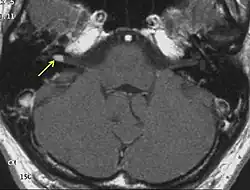

NF2 is a genetically transmitted condition. Diagnosis is most common in early adulthood (20–30 years); however, it can be diagnosed earlier. NF2 can be diagnosed due to the presence of a bilateral vestibular schwannoma, or an acoustic neuroma, which causes a hearing loss that may begin unilaterally.[14] If a patient does not meet this criterion of diagnosis, they must have a family history of NF2, and present with a unilateral vestibular schwannoma and other associated tumors (cranial meningioma, cranial nerve schwannoma, spinal meningioma, spinal ependymomas, peripheral nerve tumor, spinal schwannoma, subcutaneous tumor, skin plaque). This being said, more than half of all patients diagnosed with NF2 do not have a family history of the condition.[14] Although it has yet to be included into clinical classification, peripheral neuropathy, or damage to the peripheral nerves, which often causes weakness, numbness and pain in the hands and feet, may also lead to a diagnosis of NF2. In children, NF2 can present with similar symptoms, but generally causes "visual disturbances (cataracts, hamartomas), skin tumors, mononeuropathhy (facial paresis, drop foot), symptomatic spinal cord tumors, or non-vestibular intracranial tumors".[14]

Bilateral vestibular schwannomas are diagnostic of NF2.[15]

- Detection of bilateral acoustic neuroma by imaging-procedures